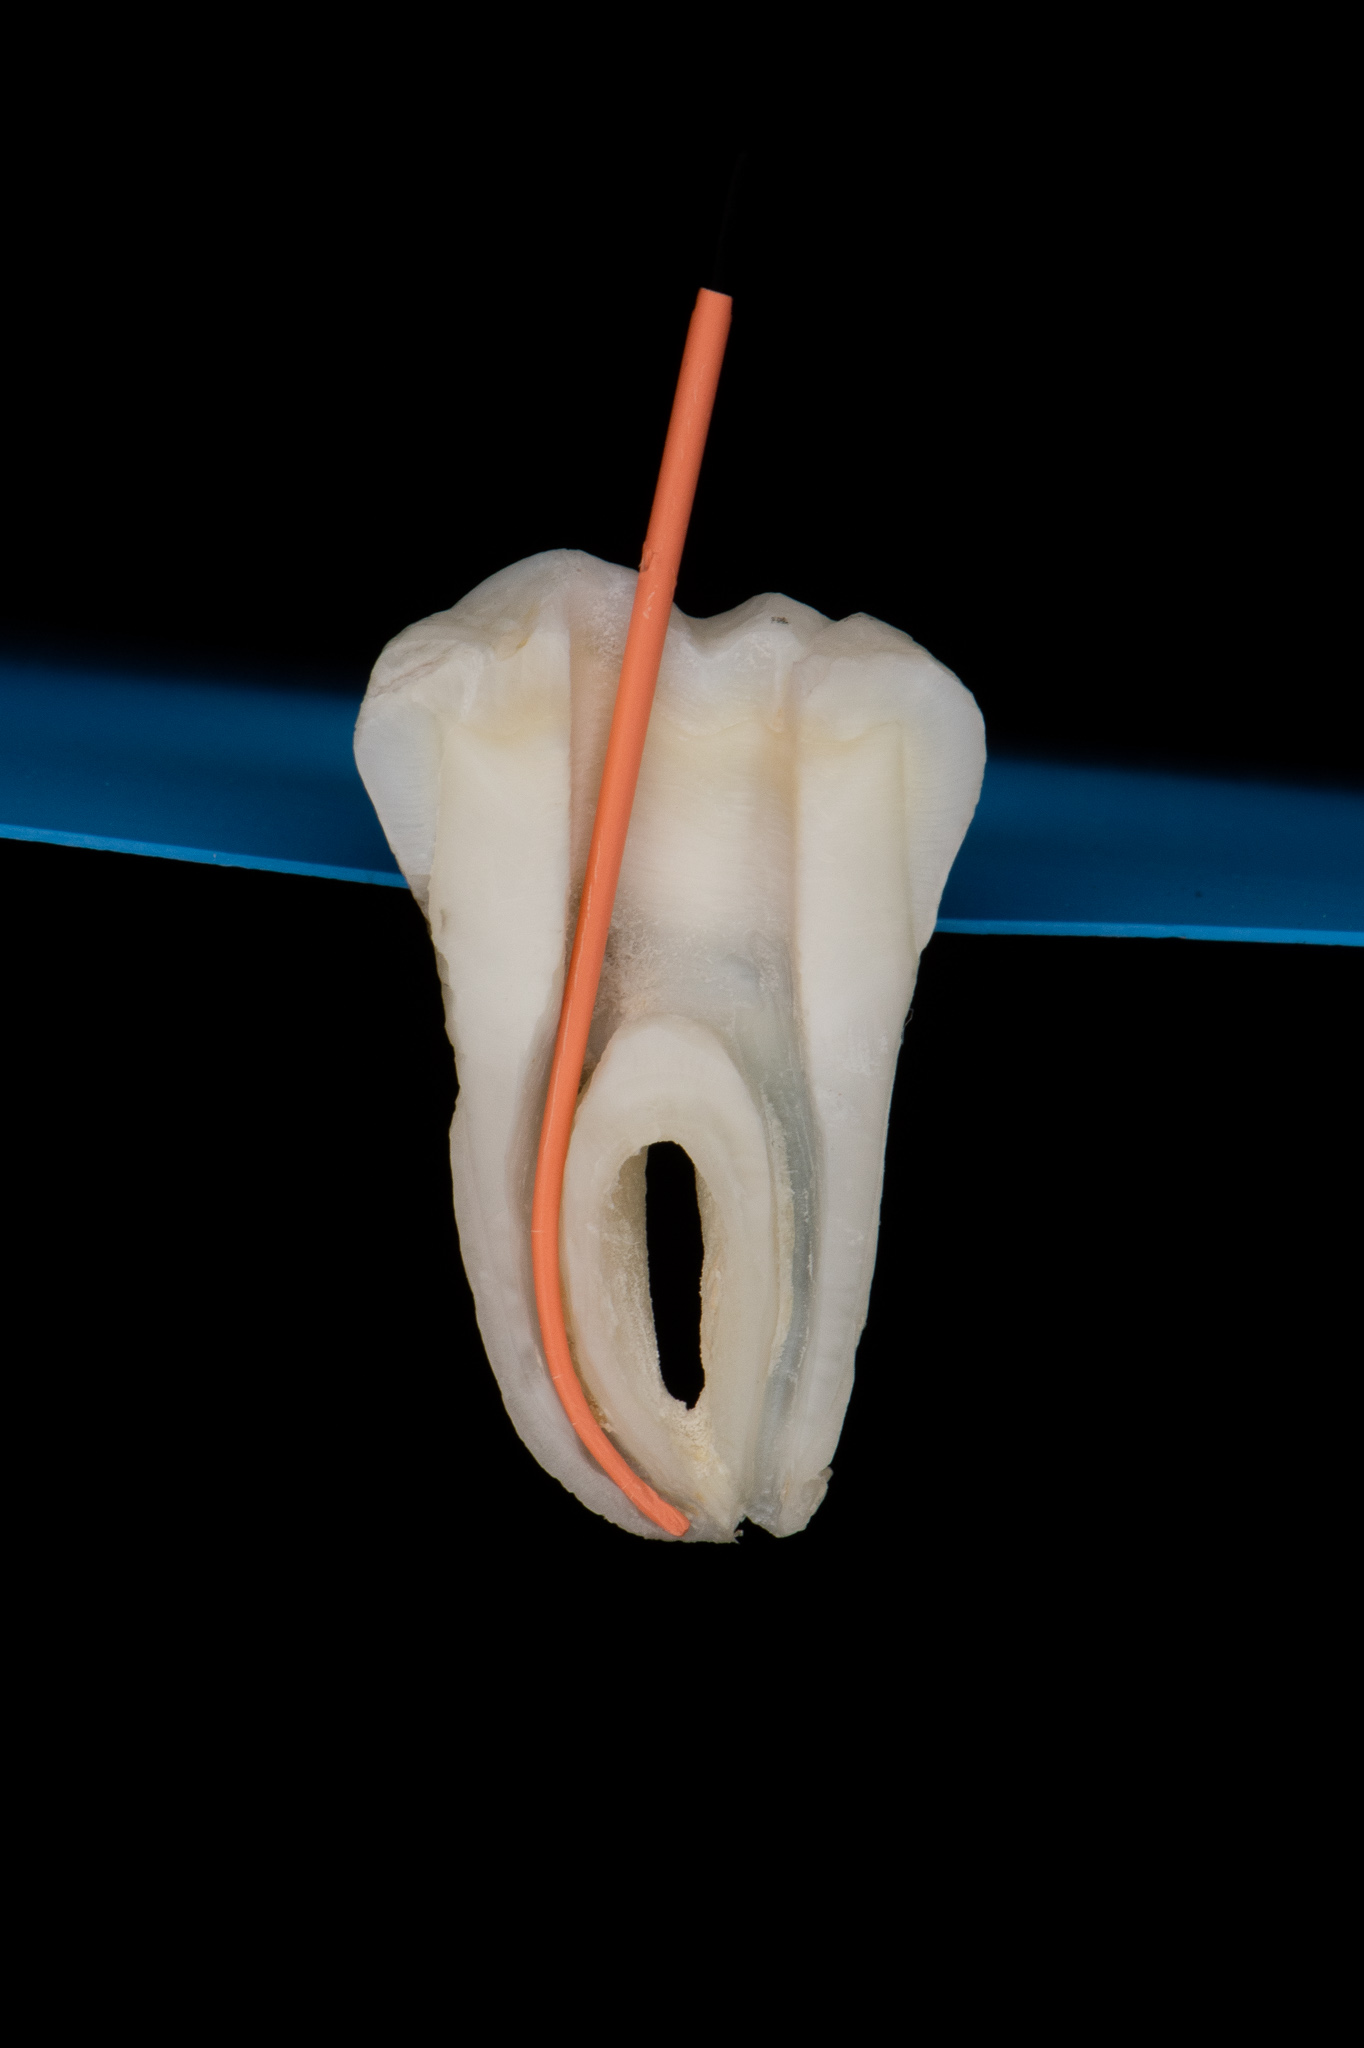

Endodoncja czyli leczenie kanałowe pozwala, na wiele lat, utrzymać w zdrowiu zęby martwe, które w przeciwnym razie wymagałby usunięcia. W naszym gabinecie prowadzimy leczenie kanałowe pierwotne jak również powtórne (ReEndo) z wykorzystaniem nowoczesnych technik i narzędzi takich jak mikroskop zabiegowy, rotacyjne systemy udrażniania kanałów czy wypełnienie płyną falą gutaperki.

Pacjent zgłosił się do gabinetu w celu zaopatrzenia złamanego zęba (kła) w koronę protetyczną. W badaniu radiologicznym widoczna jest resorpcja materiału wypełniającego kanał po dawnym leczeniu endodontycznym oraz tworząca się zmiana zapalna w okolicy wierzchołka korzenia; z uwagi na konieczność wykorzystania zęba jako filar protetyczny przeprowadzono powtórne leczenie kanałowe (ReEndo) z wykorzystaniem nowoczesnych narzędzi rotacyjnych oraz mikroskopu zabiegowego. Kanał wypełniono szczelnie techniką obturacji płynną falą gutaperki (wypełnienie na ciepło).